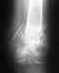

перелом бедра

Мой брат сломал бедро (со смещением), нижняя часть 4 мая. Сразу операцию делать не стали решили подождать, не торопиться.

У него держалась температура 38-39, ее сбивали (антибиотиками), делали капельницу 5 дней температуры уже нет, 19,05,06, отек значительно рассосался гноя в ноге нет анализы в норме, кроме СОЕ=35, но так говорят бывает, операцию оложили еще на 2 недели, зав отделением говорит пусть полежит, сил наберется, другие врачи согласны что уже надо делать операцию но не спорят с ним, что делать?